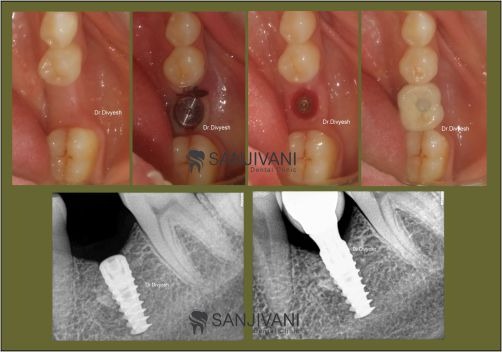

When the choice is between keeping a tooth or replacing it, a steady hand matters. The clinic’s approach combines prevention with practical restoration options, offering solutions that fit real life. The staff walks through timelines, costs, and aftercare so plans feel doable. A standout dental implants rajkot focus is patient safety, from sterilization protocols to comfortable anesthesia. By centering the patient’s bite, comfort, and daily routines, the team helps people return to eating, talking, and smiling with confidence that lasts beyond a single visit.

sanjivani dental hospital Rajkot